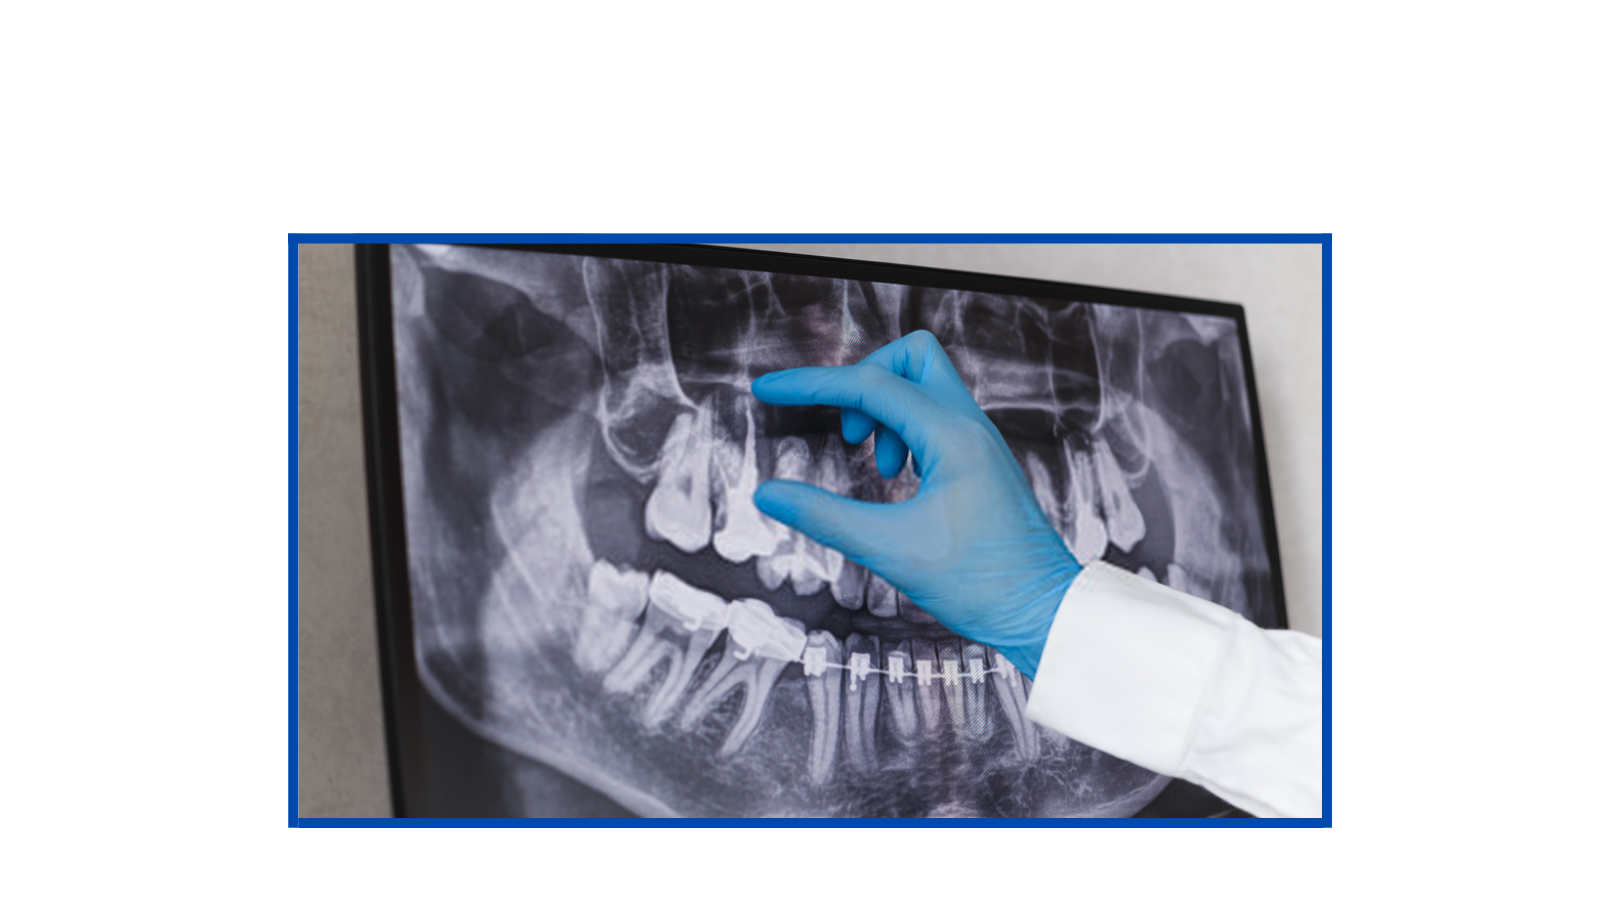

Radiografia Panorâmica

A radiografia panorâmica é um raio-x que engloba o complexo maxilomandibular, ou seja, trata-se de um exame de imagem que possibilita visualizar estruturas internas da região da boca. É uma das técnicas radiográficas mais solicitadas e difundidas em todas as especialidades da odontologia.